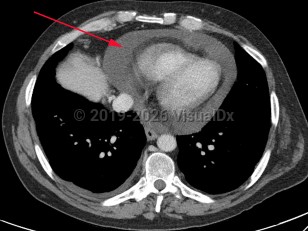

Pericardial effusion

A pericardial effusion (PE) is an accumulation of an abnormal amount of fluid within the pericardial cavity, usually from inflammation. It may be caused by local or systemic disorders or may be idiopathic. It is typically secondary to injury to the pericardium, such as pericarditis. In more than half of cases, PE is associated with a known or suspected underlying process.

PE may be asymptomatic unless there is an association with inflammation or tamponade. Symptoms typically arise due to compression of neighboring organ structures or diastolic heart failure. Common symptoms include chest pain or discomfort, light-headedness or syncope, palpitations, cough, shortness of breath, nausea, abdominal fullness, dysphagia, hoarseness, anxiety, confusion, and hiccups.